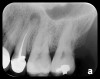

Some representative radiographic PSP images are exhibited here for demonstration of the anatomy and pathology that can be visualized with this technology. Many of these images would not have been possible if HW technology were used (Figure 3 through Figure 8).

As displayed here, the 2D radiographic images in Figure 3 through Figure 8 can alert the clinician to the need for a further 3D CBCT analysis to properly ascertain the anatomy and extent of the pathology that is initially visible in the intraoral radiographs. Proper treatment or referral to the appropriate specialty practice can follow.5,6 No. 2 PSP radiographs, when used in a conventional full-mouth series of radiographs on a patient with a relatively complete dentition, will routinely allow visualization of the anatomy of third molars, mandibular canal, maxillary sinuses, full dental root morphology, and bone anatomy beyond the apices2,16,17 (Figure 9 and Figure 10).

Fig 4. Severe dilaceration of root of tooth No. 17 and

curvature of roots of No. 18. Mandibular canal and inferior border of mandible are

easily visualized. If extraction of No. 17 is planned, a 3D CBCT study is required

due to proximity of tooth root to vascular and inferior alveolar nerve contents of

mandibular canal and possibility of surgical complications.

Figure 4